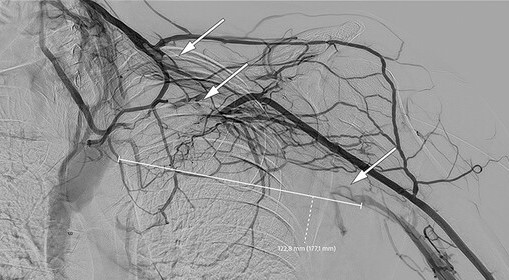

Bildet øverst viser diffus hevelse i bløtvevet uten hudforandringer eller glandelsvulst. I tillegg er det prominerende vener på venstre del av bryst og skulder. På mistanke om venetrombose ble det bestilt en venografi, som viste trombose i vena axillaris, v. subclavia og v. brachiocephalica på venstre side med dilatasjon av kollaterale kar (se bildet nederst, video under).

Fire dager senere, tilsvarende uke 14 + 2, kontaktet hun lege på grunn av økende smerte og hevelse på venstre side av hals, skulder og ansikt. Hun ble henvist til akuttmottak, og ved undersøkelse ble det beskrevet diffus ømhet i bløtvev i nedre del av ansikt og hals samt over m. pectoralis på venstre side. Det ble ikke målt D-dimer, men på mistanke om venetrombose ble enoksaparin gjeninnsatt, med 100 mg × 1 subkutant. På mistanke om en hudinfeksjon ble det også gitt penicillin 1,2 g × 4 intravenøst. Det ble bestilt ny ultralydundersøkelse, som etter anbefaling fra radiolog ble omgjort til en venografi.